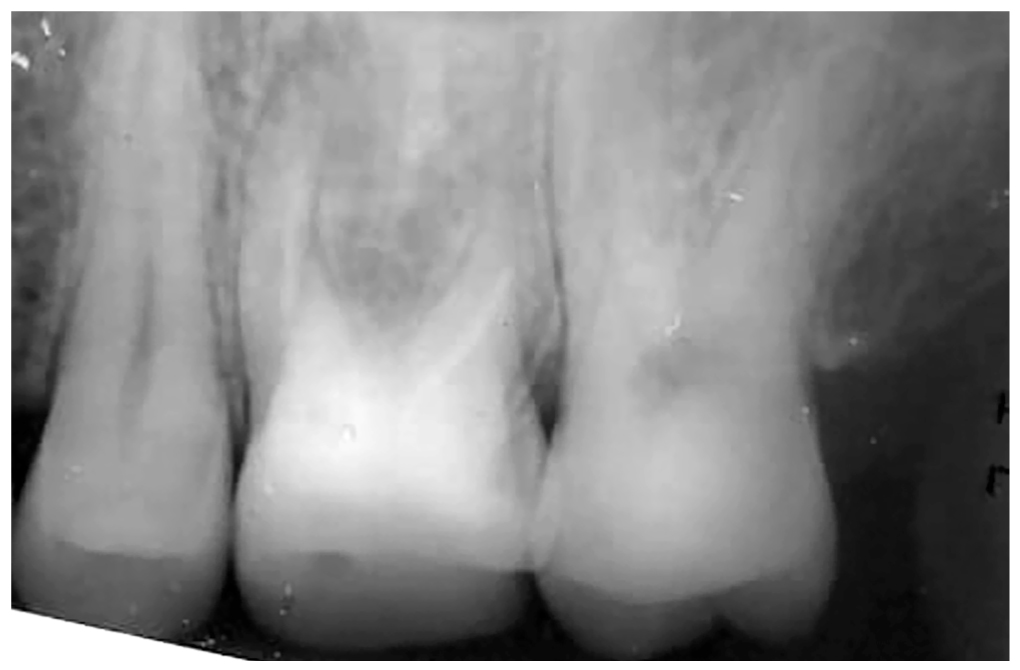

После выполнения внутриротовой рентгенографии установлено, что коронковая часть зуба 2.6 разрушена и восполнена малоконтрастным пломбировочным материалом. Нёбный канал 2.6 запломбирован, дистальный щёчный канал 2.6 обтурирован наполовину, мезиально-щёчный канал корня свободен от пломбировочного материала. В области верхушки мезиально-щёчного корня зуба 2.6 отмечалось разрежение костной ткани с нечёткими контурами диаметром до 4 мм. Внутрикорневые штифты не определяются (рис. 1).

Рис. 1. Пациент Е., 34 года: внутриротовая рентгенограмма зуба 2.6.